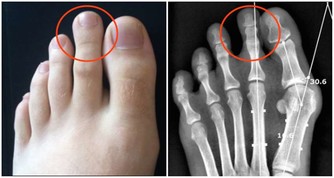

*****標誌2:你沒有“三高”慢性病。*****這裡的“三高”指的是高血壓、糖尿病和高尿酸,因為這三種疾病都會受累腎臟,比如高血壓和糖尿病都會損傷腎臟的微小血管,而尿酸需要腎臟排出,長期高尿酸會導致尿酸結晶沉積於腎臟,對腎臟的健康極為不利。